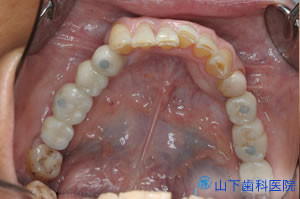

| 初診時正面観 すでに抜歯された部分は前後の歯を削って冠を被せるブリッジ、それができない最後臼歯の欠損は放置、それ以外に残るすべての歯に何らかの治療がなされています。保険の銀歯もあれば、保険が効かないセラミックで化粧した金属冠のメタルボンド(さし歯)もあり、 プラスチックの詰めもの(コンポジットレジン)はどれも茶色く変色しています。 |

| 初診時上顎咬合面観 | ![]() |